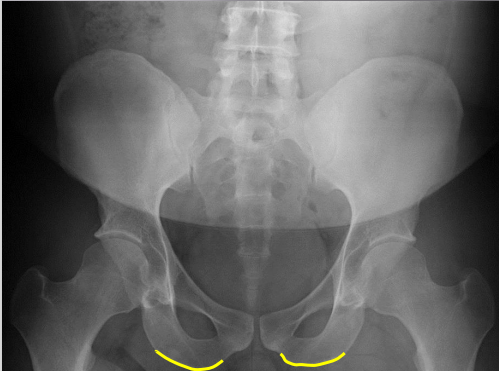

Ischial tuberosities

Superior iliac crests